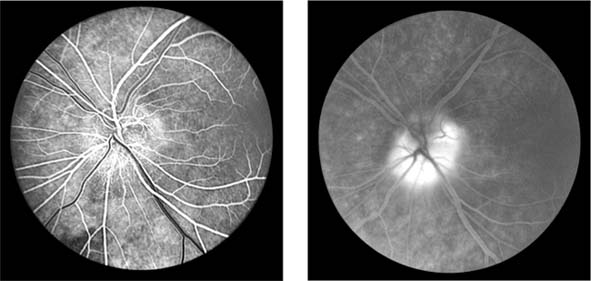

Figure 15-10: Accelerated hypertension. Fluorescein angiogram in a young man showing arteriolar constriction, dilation of capillaries with microaneurysms, and areas of closure. Marked disk edema is present.

In contrast, elderly patients with arteriosclerotic vessels are unable to respond in this manner, and their vessels are thus protected by the arteriosclerosis. It is for this reason that elderly patients seldom exhibit florid hypertensive retinopathy (Figure 15-11).

Figure 15-11

Figure 15-11: Accelerated hypertension. Fluorescein angiogram in an elderly wom.an showing marked arteriolar constriction and irregularity but few signs of florid retinopathy.

Fluorescein angiography has made possible accurate documentation of these microcirculatory changes. In young patients with hypertension, arteriolar attenuation and occlusion are seen, and capillary nonperfusion can be verified in relation to a cotton-wool spot, which is surrounded by abnormal dilated capillaries and microaneurysms with increased permeability on fluorescein angiography.

Resolution of the cotton-wool spots and the arteriolar changes occurs with successful hypotensive therapy. In elderly patients, the underlying arteriosclerotic changes are irreversible.